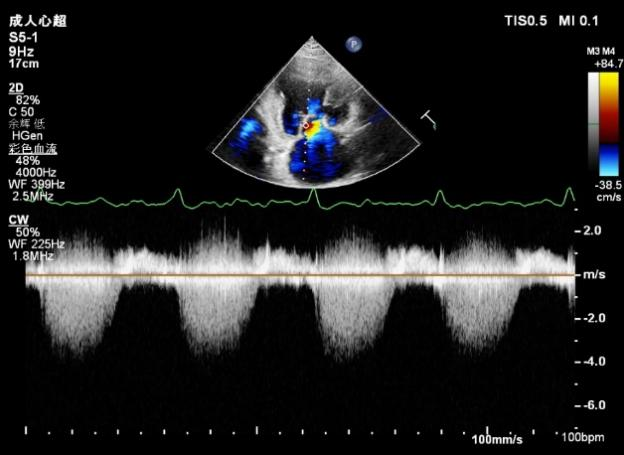

肺静脉血流频谱逐渐恢复正向,后测量平均跨瓣压差:2mmHg

二尖瓣瓣口平均跨瓣压差:3mmHg